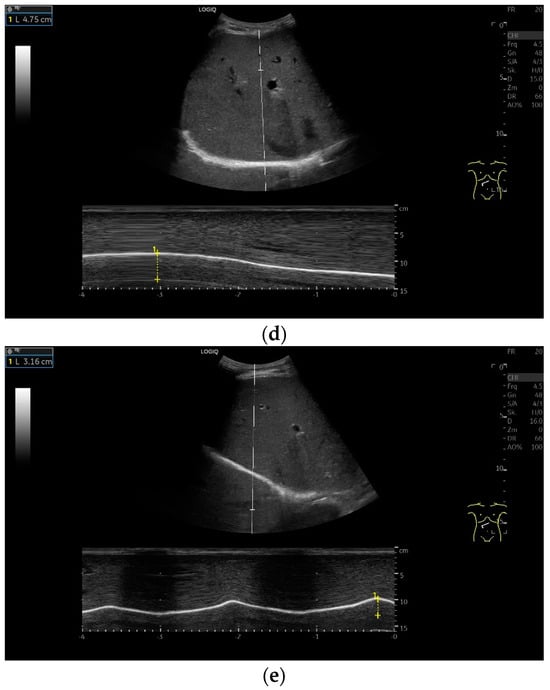

With high-resolution linear transducers, the diaphragm presents itself as a hypoechoic band. It is covered on both sides by a very thin hyperechoic layer. This corresponds to the peritoneum and the parietal pleura, respectively. Depending on the resolution, a further delicate hyperechoic layer is usually visible centrally in the muscle, which is most often considered to be a fibrous layer in the center of the diaphragm (Figure 1).

Lateral transducer position in the zone of apposition: The transducer is positioned longitudinally and laterally in the area of the mid-axillary line or slightly ventral to it between the anterior and mid-axillary lines, approximately in the 8th or 10th intercostal space. The diaphragmatic reflex is located on the inner side of the ribs below the pulmonary glide with pulmonary reverberations. This localization of origin of the diaphragm from the inner side of the rib cartilage is referred to as the zone of apposition (Figure 3). As this localization is only a few centimeters below the skin surface, high-resolution linear transducer use is highly recommended. In this position, the diameter of the diaphragm is measured during inspiration and expiration [2,3,4,5] (Figure 4). The thickness of the diaphragm varies, with caudal parts being thicker than cranial parts. The measurement of diaphragm thickness is highly variable depending on the intercostal space chosen, with thickness varying by up to 6 mm between the intercostal spaces [6]. It is therefore important to select the same position for comparable measurements and, if necessary, to mark the location for the transducer position [7]. Obesity limits assessment of the diaphragm [2].

Subcostal transducer position: An abdominal sector or cardiac transducer (2–5 MHz) is used in the subcostal window. This position is used to assess diaphragmatic excursion. The transducer is placed between the linea medioclavicularis and linea axillaris anterior. The diaphragmatic excursion can then be visualized and measured in M-mode (Figure 5). The gallbladder and inferior vena cava are important landmarks. It is important to guide the ultrasound probe as perpendicularly as possible. The M-mode axis should meet the diaphragm at an angle of 90%. In this position, diaphragm thickness in inspiration and expiration can also be measured using M-mode, and diaphragm shortening can be calculated. However, in normal adults, the diaphragm can usually only be visualized in this position using abdominal sector transducers and is less accurately delineated than with a linear transducer from the lateral side in the anterior axillary line.

Subxiphoid: The diaphragm can be positioned directly subxiphoidally with a slightly sagittal transducer position on both sides next to the attachment to the sternum. The diaphragm limb can be demarcated to the right in the epigastrium in cross section between the aorta and the inferior vena cava. However, this is primarily of differential diagnostic importance, e.g., in relation to lymphomas, not for the actual assessment of the diaphragm (Figure 6).

To assess the diaphragm and its function, the diaphragm’s thickness, contraction and excursion are determined. Diaphragm thickness is mainly measured in the zone of apposition and excursion in the subcostal position. The diaphragm thickness is measured at end-expiratory (Tendexpir) and end-inspiratory (Tendinspir) points. Expiratory and inspiratory measurements should be taken with exactly the same transducer position. The measurement is taken at the outer edges of the hypoechoic muscle and at an angle of 90° to the diaphragm’s surface (Figure 4).